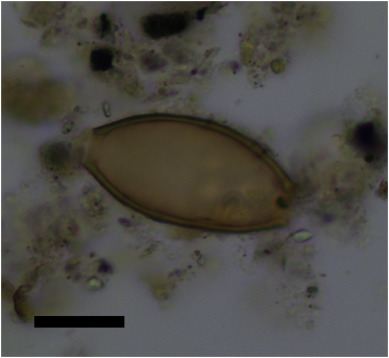

They found that eggs from two species of parasitic worm (helminths) were present: whipworm (Trichuris trichiura), and roundworm (Ascaris lumbricoides). Whipworm was present from the Neolithic, and roundworm from the Bronze Age.

Abstract Little is known about infectious disease and parasites in the prehistoric inhabitants of the islands of the Aegean, in contrast to later time periods. It is only with the development of Greek medical texts in the 5th and 4th centuries BC we start to find evidence for the diseases that affected the population of region. Foremost amongst these authors was the medical practitioner Hippocrates, who lived on the island of Kos. The descriptions of the many diseases he and his students encountered were recorded in their medical texts in the 4th and 3rd centuries BC, known as the Hippocratic Corpus. These important texts provided the core philosophy underpinning medical theories in Europe and the Arab world for the following 2,000 years. Past research to determine which species of intestinal parasitic worms were described in the Hippocratic Corpus has suggested they indicate roundworm, pinworm and Taenia tapeworm. However, until now, there has been no archaeological evidence for which species of helminths were present in ancient Greece. In this study, we analysed soil sediment adherent to the sacrum and iliac bones of the pelvis of 25 burials dating from the Neolithic to Byzantine period on the Greek island of Kea, not far from Kos. Four individuals (16%) were positive for the eggs of intestinal helminths, dating from the Neolithic (4th millennium BC), Late Bronze Age, and the Roman Period. The species identified were whipworm (Trichuris trichiura) and roundworm (Ascaris lumbricoides). We consider reasons as to why fewer species of parasite appear to have been present on Kea than was the case for northern Europe at the same time period. This study of ancient parasites shows how we can combine archaeology with history of medicine to better understand the discoveries of key early scientists and medical practitioners.